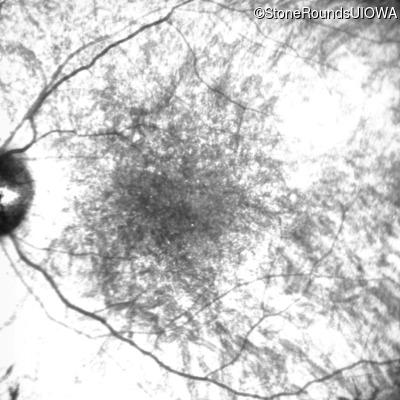

Infrared Fundus Photograph - Right - 10/140 sc

Exemplar

Infrared Fundus Photograph - Left - 10/180 sc